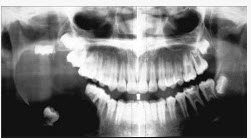

男,18岁,右颌下区反复肿胀半年,2天前再次发作,病程进展快,出现张口受限。X线片示右下颌角区沿颌骨长轴有单囊阴影,包绕右下颌第三磨牙牙冠。该病人最可能的诊断是()

正确答案:C